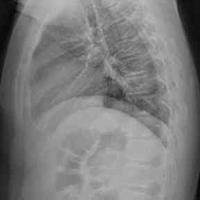

一名患者因摔伤肘部至医院就诊,接下来的治

一名患者因摔伤肘部至医院就诊,接下来的治疗是什么?...

由 medjpg 发表于 2026-03-24 22:32